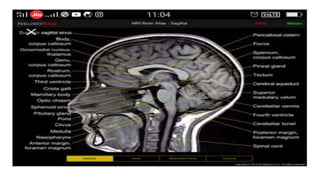

Sagittal T1 (Normal)

T1

• Provides the most anatomically-relevant images

• Fluid (in CSF and orbits) is dark

• Grey matter is darker than the white matter